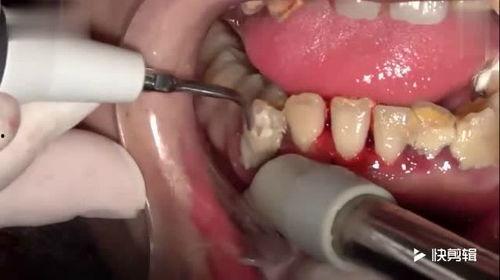

牙医的“魔法手”

视频中,牙医的“魔法手”轻轻地在洗牙石上挥舞,仿佛在施展着某种神奇的魔法。只见洗牙石上的污渍一点点被清除,露出了原本洁白的牙齿。这个过程真是让人看得热血沸腾,仿佛自己也置身于牙科诊所中。

你知道吗?洗牙石其实是一种特殊的材料,它的表面有很多微小的凹槽,可以有效地吸附牙齿上的污渍。而牙医使用的洗牙工具,就是通过高速旋转产生的强大吸力,将污渍从牙齿表面吸走。这个原理真是让人惊叹不已!